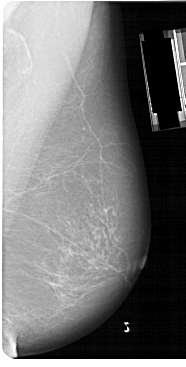

A_1149_1.RIGHT_MLO

RIGHT_MLO LINES 5491 PIXELS_PER_LINE 2776 BITS_PER_PIXEL 12 RESOLUTION 43.5 NON_OVERLAY